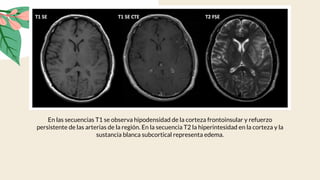

En las secuencias T1 se observa hipodensidad de la corteza frontoinsular y refuerzo

persistente de las arterias de la región. En la secuencia T2 la hiperintesidad en la corteza y la

sustancia blanca subcortical representa edema.